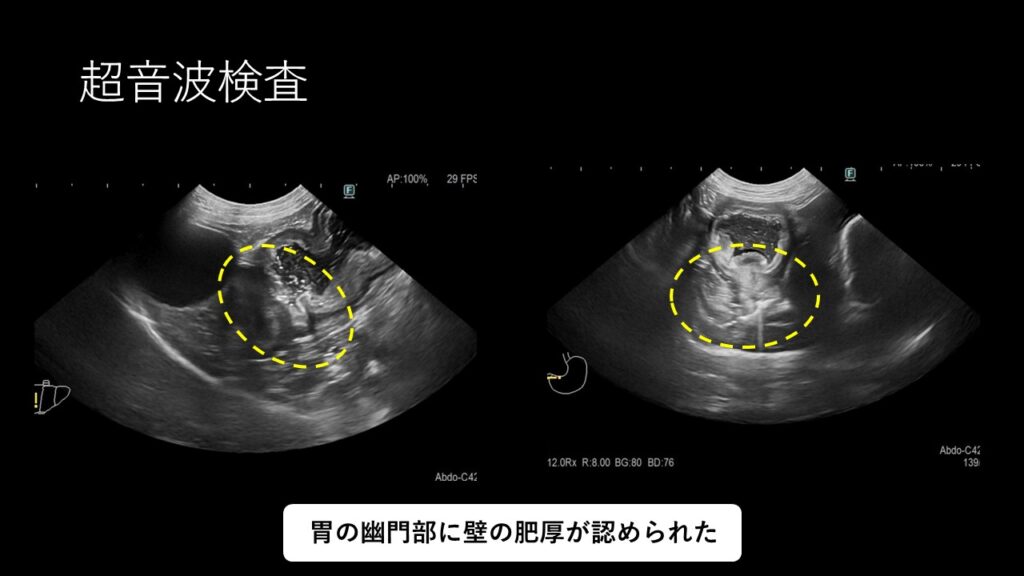

超音波検査の結果、胃の幽門部に壁の肥厚が認められました。

検査の結果、幽門部の壁の肥厚(粘膜の過形成や腫瘍、ポリープなど)による通過障害が疑われました。